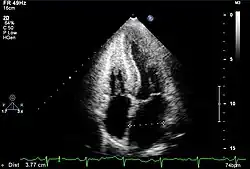

| Apparent left ventricular hypertrophy and “snowstorm” appearance of the myocardium are suggestive of an infiltrative cardiomyopathy. | |